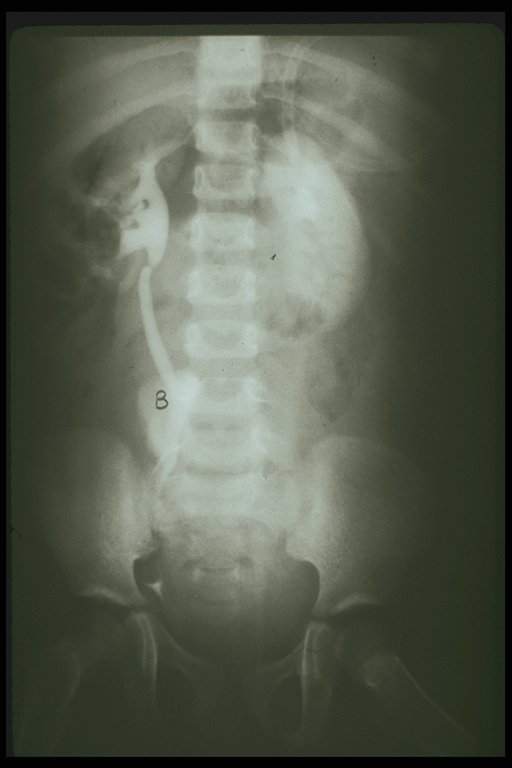

X-ray showed a fracture line on the ischium (arrow) and both pubic rami in a child with severe pelvic fracture and massive retroperioneal hemorrhage

Angiogram in the child with pelvic fracture demonstrates the large retroperitoneal hematoma on the left side displaced the bladder upward